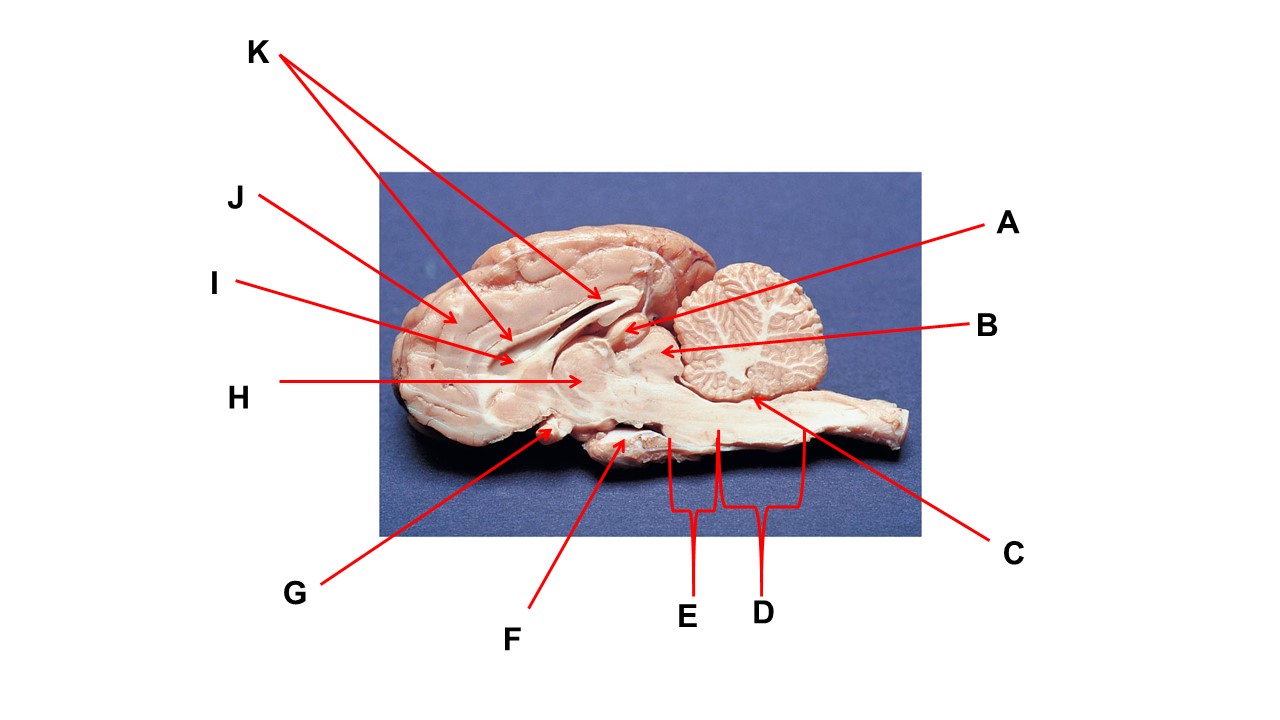

Name the structure at the tip of arrow A.

pineal gland

The cavity at the tip of arrow I is the _____.

lateral ventricular

The cavity at the tip of arrow I is filled with ______.

cerebrospinal fluid

Name the region within bracket D

medulla

Name the structure at the tip of arrow F

mammillary body

Name the structure at the tip of arrow A.

pineal gland

Name the structure at the tip of arrow G

optic chiasma

Name the nerve at the tip of arrow H.

optic